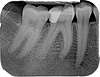

Radio dentaire

Radio des dents